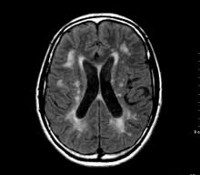

Этиологические факторы ДЭП тем или иным способом приводят к ухудшению мозгового кровообращения, а значит к гипоксии и нарушению трофики клеток головного мозга. В результате происходит гибель мозговых клеток с образованием участков разрежения мозговой ткани (лейкоареоза) или множественных мелких очагов так называемых «немых инфарктов».

Наиболее уязвимыми при хроническом нарушении мозгового кровообращения оказываются белое вещество глубинных отделов головного мозга и подкорковые структуры. Это связано с их расположением на границе вертебро-базилярного и каротидного бассейнов. Хроническая ишемия глубинных отделов мозга приводит к нарушению связей между подкорковыми ганглиями и корой головного мозга, получившему название «феномен разобщения». По современным представлениям именно «феномен разобщения» является главным патогенетическим механизмом развития дисциркуляторной энцефалопатии и обуславливает ее основные клинические симптомы: когнитивные расстройства, нарушения эмоциональной сферы и двигательной функции. Характерно, что дисциркуляторная энцефалопатия в начале своего течения проявляется функциональными нарушениями, которые при корректном лечении могут носить обратимый характер, а затем постепенно формируется стойкий неврологический дефект, зачастую приводящий к инвалидизации больного.

В рамках диагностики дисциркуляторной энцефалопатии проводится консультация офтальмолога с офтальмоскопией и определением полей зрения, ЭЭГ, Эхо-ЭГ и РЭГ. Важное значение в выявлении сосудистых нарушений при ДЭП имеет УЗДГ сосудов головы и шеи, дуплексное сканирование и МРА мозговых сосудов. Проведение МРТ головного мозга помогает дифференцировать дисциркуляторную энцефалопатию с церебральной патологией другого генеза: болезнью Альцгеймера, рассеянным энцефаломиелитом, болезнью Крейтцфельдта - Якоба. Наиболее достоверным признаком дисциркуляторной энцефалопатии является обнаружение очагов «немых» инфарктов, в то время как признаки мозговой атрофии и участки лейкоареоза могут наблюдаться и при нейродегенеративных заболеваниях.